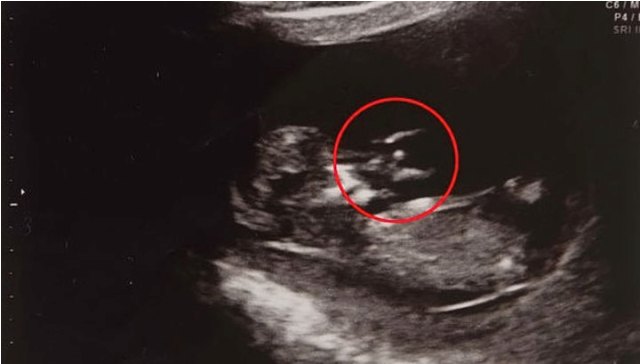

«Ներարգանդային լուսանկարներում հրեշտակին մայրս է առաջինը տեսել։ Ես այդ ժամանակ զբաղված էի բժիշկների հետ զրուցելով: Նրանք հայտնել էին, որ երեխան չափից դանդաղ է աճում, և դա կարող է ազդել նրա զարգացման վրա: Երբ ես տուն եկա, մայրս նայեց լուսանկարին և ցույց տվեց ինձ հրեշտակին: Ես չէի հավատում աչքերիս», – պատմել է Հոլմանը` նշելով, որ այդ պատկերը ոգևորել է իրեն, և վստահություն ներշնչել, որ ամեն ինչ լավ է լինելու։